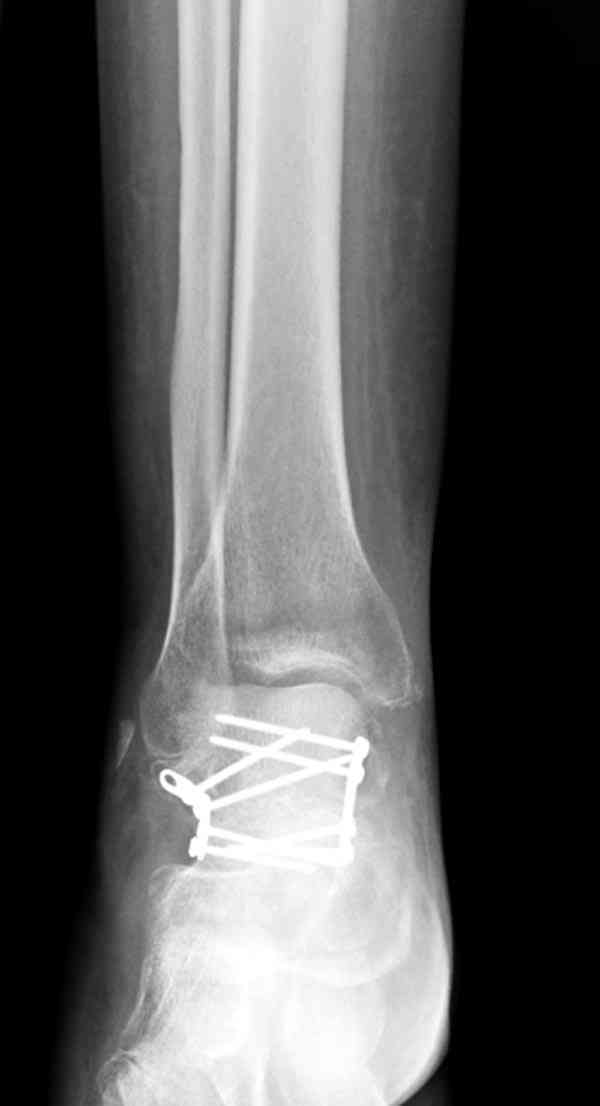

Случай с множественным оскольчатым переломом тарана оперированный из двойного доступа.

Через 8 мес.: